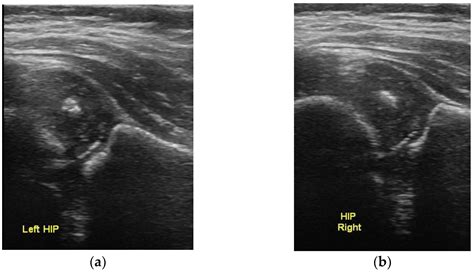

The results of an Infant Hip Ultrasound are interpreted by a radiologist or orthopedic specialist who is trained in pediatric imaging. The images are evaluated for several key factors, including:

• The shape and depth of the acetabulum

• The position of the femoral head within the acetabulum

• The presence of any abnormalities or dislocations

The results are typically categorized into one of the following:

Category Description

Normal The hip joint appears normal with no signs of dysplasia.

Mild Dysplasia The acetabulum is slightly shallow, but the femoral head is still within the socket.

Moderate Dysplasia The acetabulum is more shallow, and the femoral head may be partially dislocated.

Severe Dysplasia The acetabulum is very shallow, and the femoral head is completely dislocated.